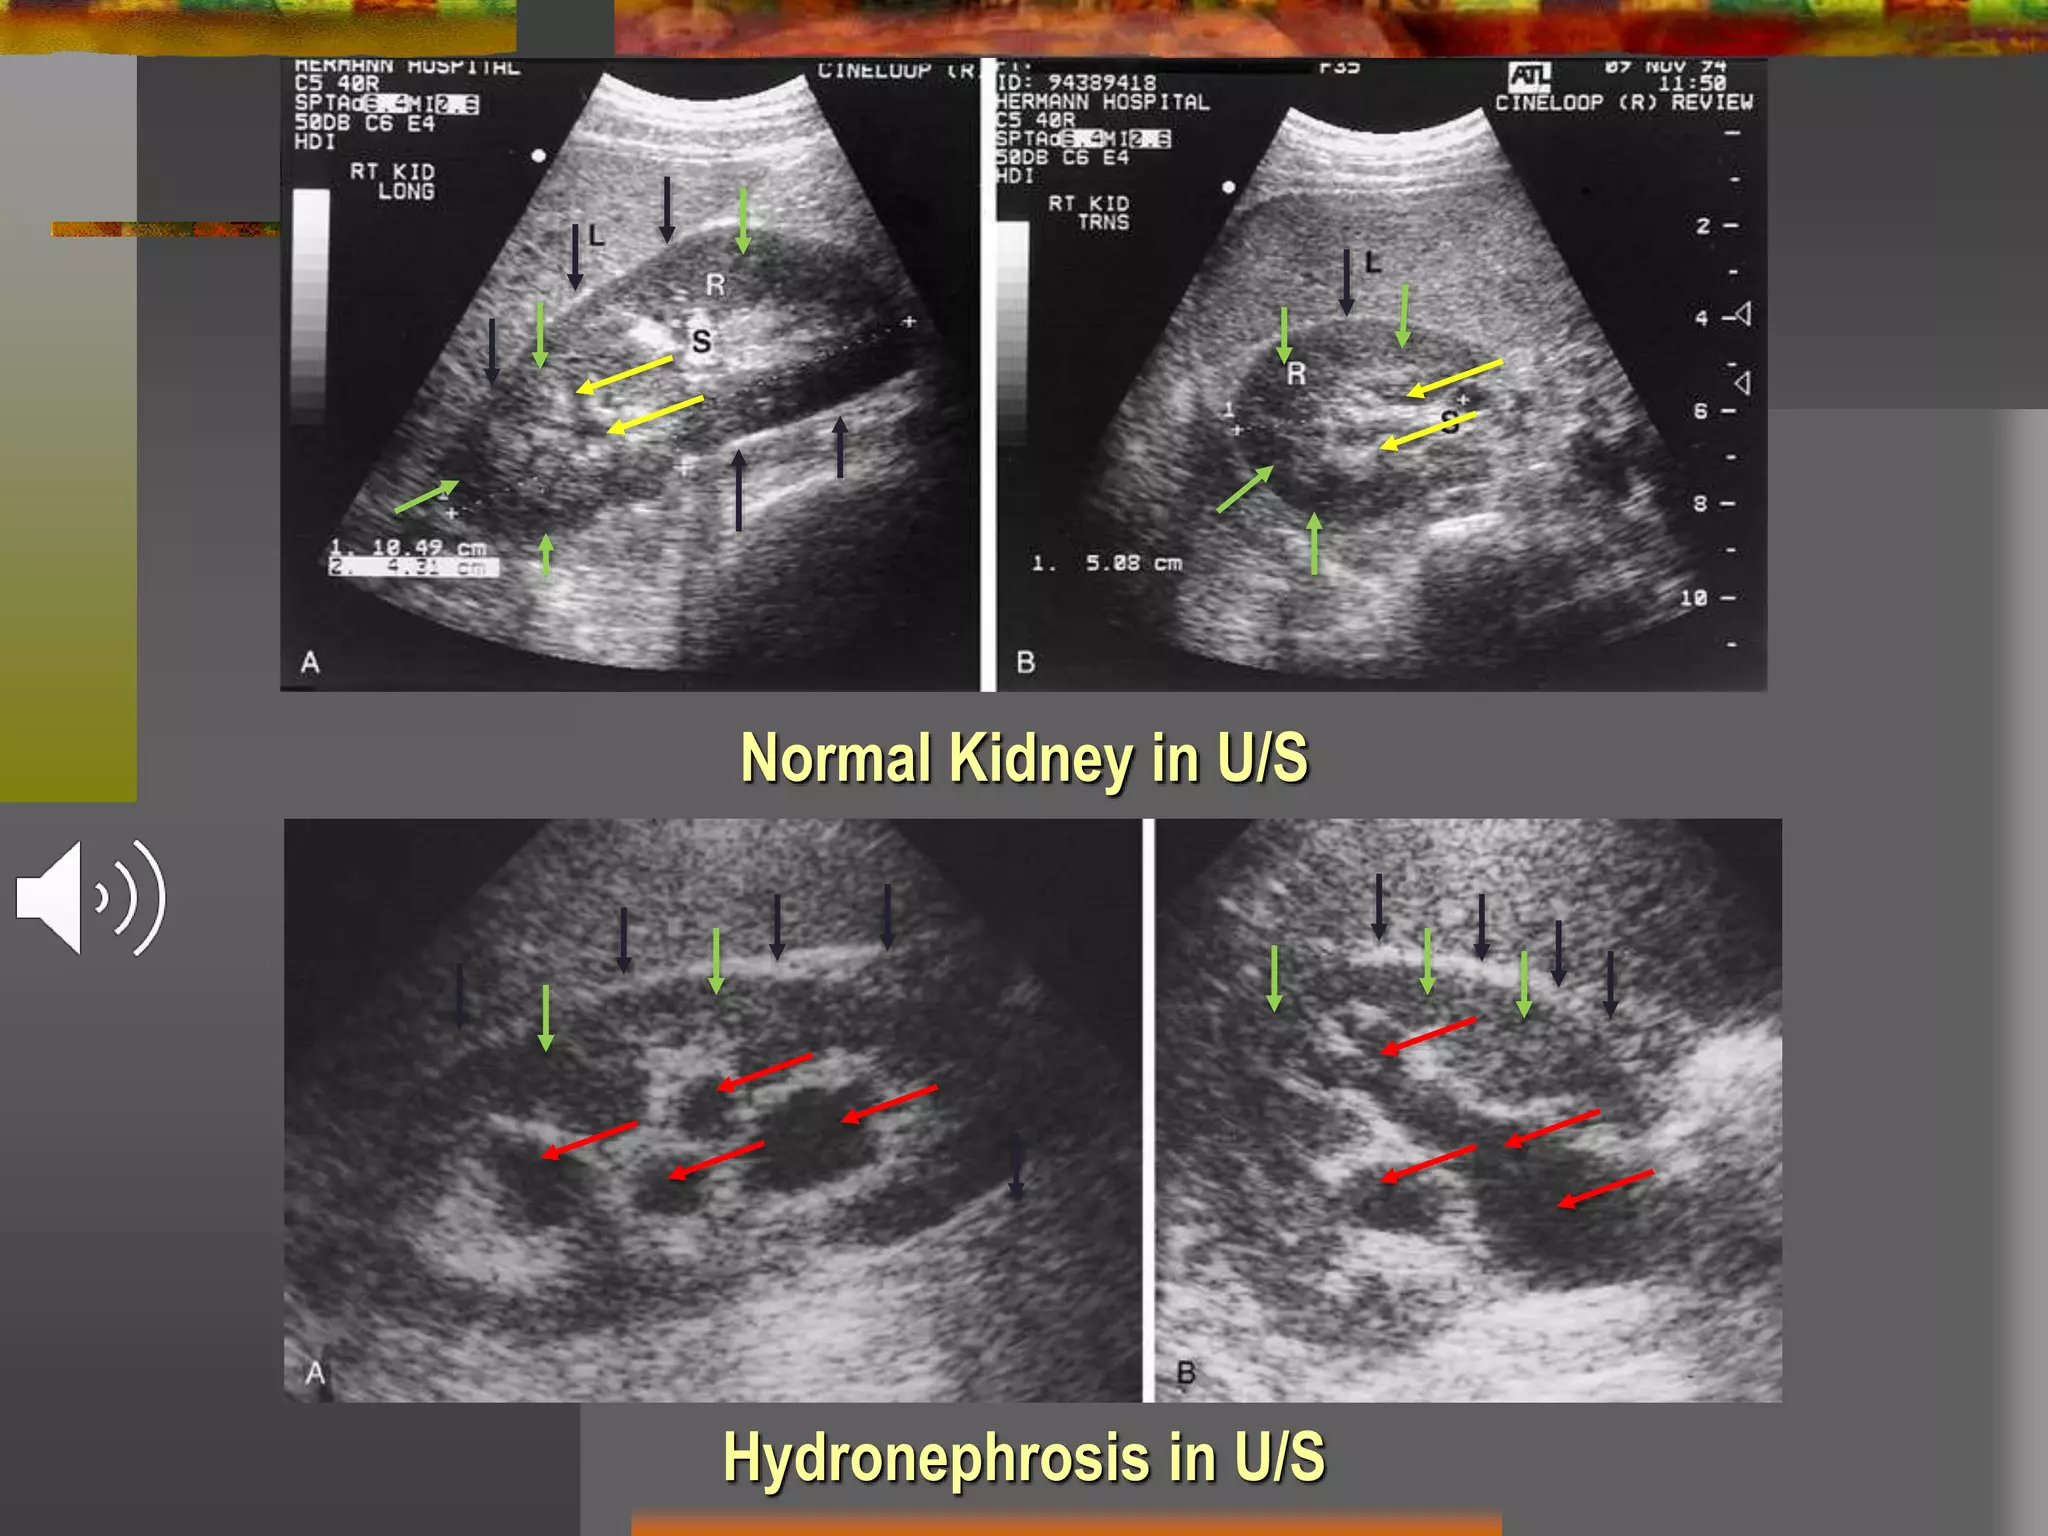

Hydronephrosis in U/S

Normal Kidney in U/S

• #17 here in you can see normal Renal U/S above and hydronephrosis in the below picture. Note the difference between normal calyces (yellow arrows) and dilated calyces (red arrows). Also note, renal capsule (black arrows) and Renal parenchyma (green arrows)